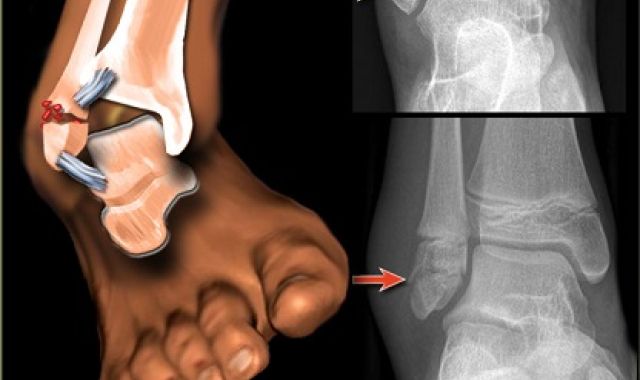

Early Mobilisation reduces the risk of complications in Ankle Fracture Fixation Surgery

Ankle fractures can occur during sporting activities, or as a result of a fall. Fractures can...